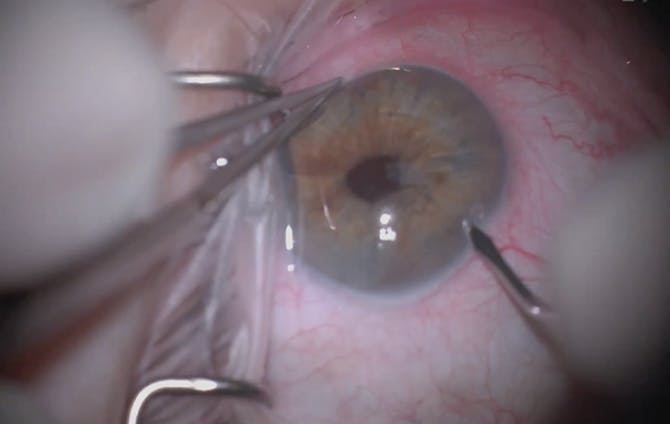

On examination, UCVA is 20/30 OU, and IOP is 14 mm Hg OU. A slit-lamp examination reveals a scarred trabeculectomy in the right eye, a well-positioned IOL in each eye, and no active hyphema. On gonioscopy, the appearance of the stent in the nasal angle of each eye is unremarkable (Figure 1). A fundus examination reveals cupping of both optic nerves. Visual field testing demonstrates stable superior arcuate scotomas in both eyes, and OCT shows cupping and thinning of the retinal nerve fiber layer in both eyes (Figures 2 and 3).

Figure 1. A Hydrus Microstent in situ in the right eye.